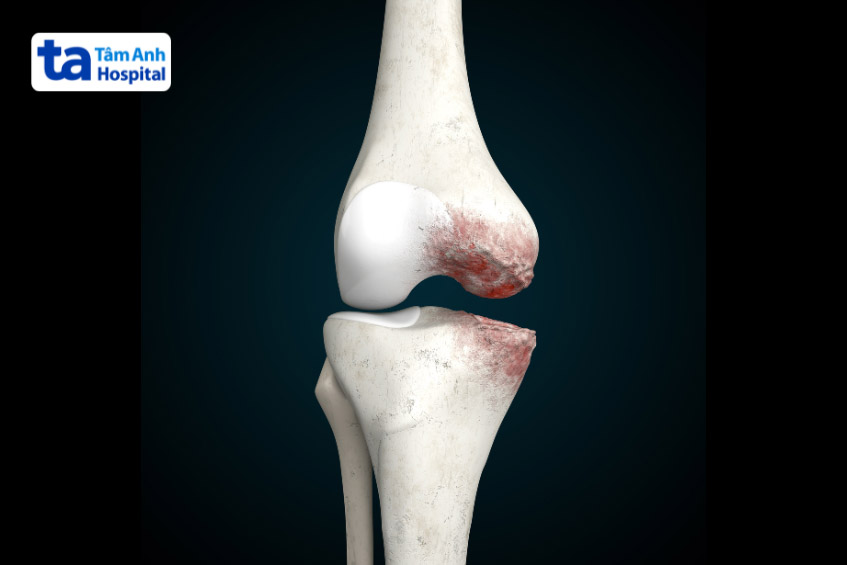

Thoái hóa khớp gối là hiện tượng sụn khớp gối bị bào mòn theo thời gian. Khi sụn bị bào mòn, các đầu xương mất đi lớp đệm bảo vệ, dẫn đến tình trạng ma sát, va chạm với nhau, gây ra tiếng lục cục, lạo xạo. Thoái hóa khớp còn khiến người bệnh thường xuyên bị đau nhức, cứng khớp, đặc biệt là sau khi ngủ dậy hoặc ngồi quá lâu.

Tiếng lục cục khớp gối có thể đến từ viêm khớp mạn tính. Bệnh lý này khiến lớp sụn bao quanh đầu xương mòn dần, tạo ma sát giữa các đầu xương, gây ra tiếng kêu lục cục bất thường.

Gai khớp gối là hiện tượng xuất hiện gai xương ở vùng khớp gối bị tổn thương. Những gai xương này hình thành để đối phó với quá trình bào mòn sụn khớp, hỗ trợ ổn định phần khớp bị thoái hóa.

Khi di chuyển, các gai xương cọ xát vào nhau tạo ra tiếng kêu lục cục. Gai khớp gối nếu không được phát hiện và điều trị kịp thời có thể dẫn đến biến dạng khớp.